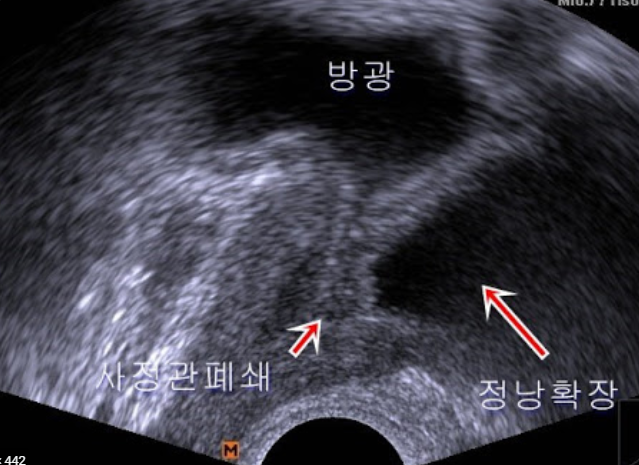

전문의와 문진을 하거나, 신체검사를 하는방법이 있습니다. 또한 소변검사도 진행합니다. 또한 요류 및 잔료량 검사와 압력 요류검사 등 여러가지가 있고, 방광경 검사와 경직장 초음파검사 또한 실시할 수 있습니다.